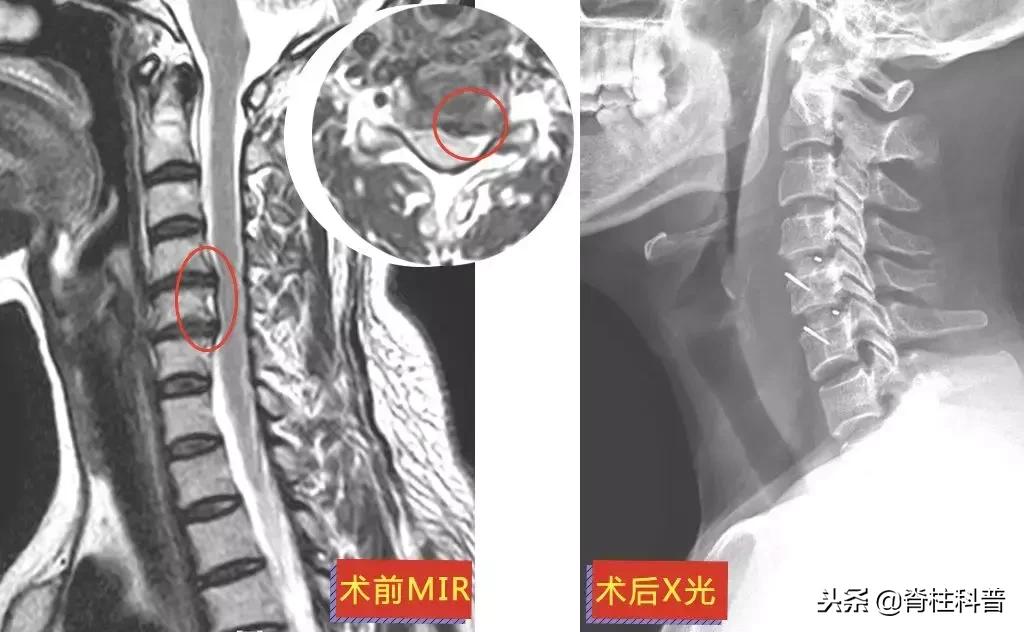

▲ 黄三叔:术前MRI与术后X光